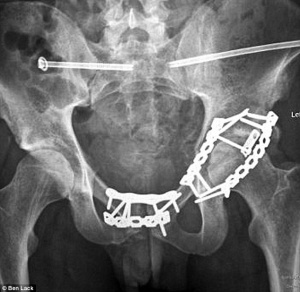

Винты вводили на пересечении этих линий через подвздошную кость в крестец (рис. 1) [3].

При разрывах крестцово-подвздошного сочленения, независимо от вида повреждения, чаще всего необходима компрессия, чтобы максимально восстановить ширину суставной щели. Компрессирующий винт вводится с шайбой, чтобы головка винта не провалилась в подвздошную кость, таким образом, чтобы захватить резьбой наиболее плотную кость в теле позвонка (рис. 2).

При трансфораминальных переломах дополнительная компрессия может понадобиться только в случае значительного диастаза на уровне перелома. В большинстве случаев предпочтительно введение позиционного винта для избежания компрессии корешков (рис. 3).

При этом решение задачи компрессии или сохранения имеющегося положения решается введением винтов с двух сторон или с использованием одного или двух винтов, проходящих через весь крестец (рис. 4) [5].